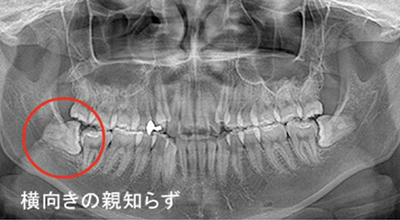

親知らずの抜歯

(難抜歯対応可能)

大人の歯が、歯ぐきや歯槽骨の中に埋まっている状態が埋伏歯と呼ばれます。必要があれば、歯茎を切開して歯を取り出します。埋伏歯の周りの神経や血管の位置によっては、一般的な抜歯と比べはるかに高い技術が要求されます。

親知らずの難症のケース

治療症例